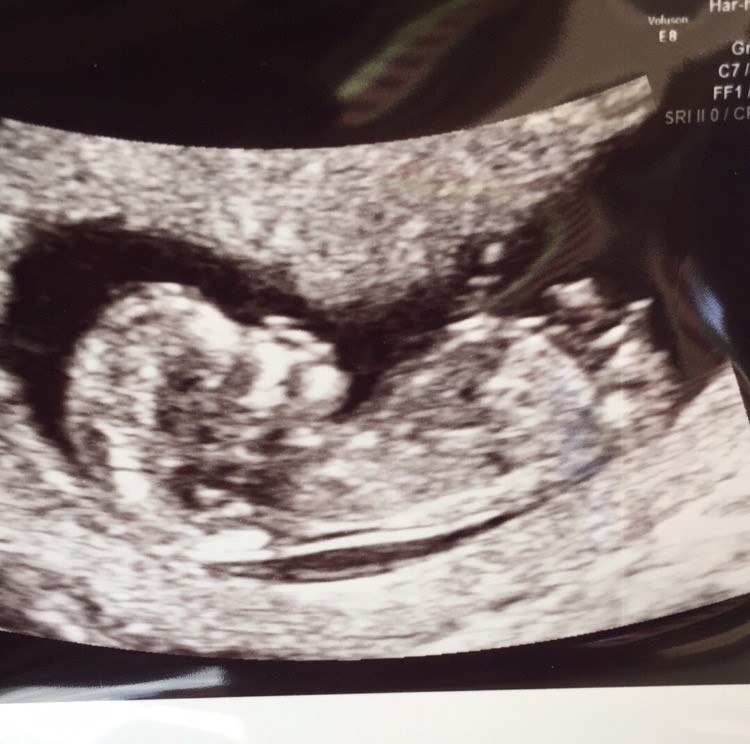

Nogen der kan se på nub om det er en pige eller dreng. ?

Vedhæftede fotos (klik for at se i fuld størrelse)